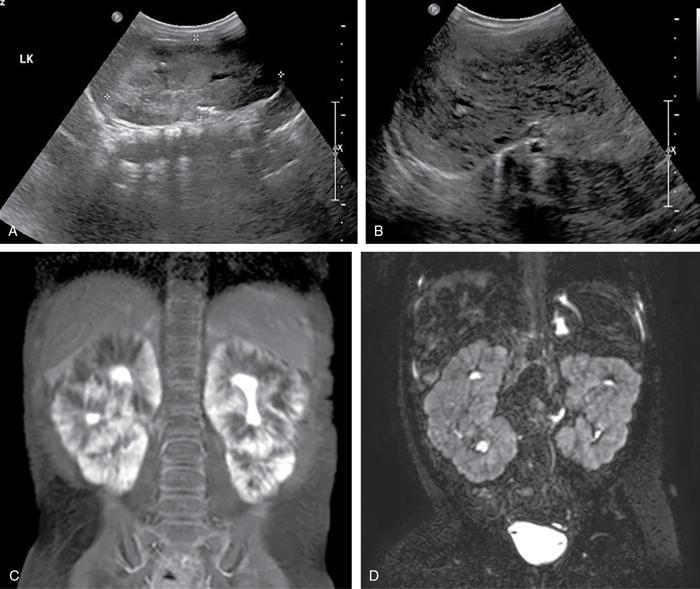

Priscilla Joshi, Vandana Jahanvi Renal anomalies encompass a spectrum which ranges from the lethal renal agenesis to incidentally detected renal anomalies secondary to aberrant embryonic migration. Imaging helps in the early diagnosis, detection of complications, surgical planning and follow-up of these patients. The kidneys develop from the pronephros, mesonephric and metanephros. These succeed each other. The intermediate mesoderm develops into the pronephros at the end of the 3rd week of gestation. This regresses a week later and is replaced by the mesonephros. The kidneys develop during the 4th week of gestation. The ureteric buds fuse with the metanephros. This occurs at the level of the first two sacral segments. In the pelvis, the kidneys are close to each other with the hila directed anteriorly. Over the next 4 weeks, the kidneys ascend into the lumbar region and move away from each other as well as rotate medially so that the hila are medially and anteriorly directed. Congenital urinary tract anomalies range from anomalies in number, anomalies in shape, cystic renal disease, collecting system anomalies and urinary bladder anomalies. These will be discussed one by one in this section. In renal hypoplasia the kidneys are small. They show a normal architecture, but the number of nephrons is reduced. The condition can be unilateral or bilateral. If unilateral the contralateral kidney shows compensatory hypertrophy. Hypoplasia if bilateral is part of genetic syndromes like renal coloboma syndrome and branchio-oto-renal syndrome. It can result in end-stage renal disease because of the reduced number of nephrons. US: A kidney which is smaller by 2 Sd as compared to the mean kidney size expected at that age. Radionuclide scan (DMSA): Rules out scarring. Less than 100 cases of this anomaly have been reported in literature. This is an extremely rare anomaly. The accessory kidneys are usually seen on the left, caudal to the left kidney. Accessory kidneys are usually smaller in size and show suboptimal function. They can be detected on ultrasound and confirmed with cross-sectional modalities like MR urography/CT urography. Function can be evaluated on postcontrast CT/MR urography or with dimercaptosuccinic acid (DMSA) and diethylene triamine penta-acetic acid (DTPA) scans. Associated urogenital or other anomalies maybe be seen. Incomplete fusion of the developing renal lobules causes a lobulated appearance of the kidneys. This has to be differentiated from renal scarring. Persistent foetal lobulations are seen as a smooth indentation of the renal outline. This is seen between the renal pyramids on ultrasound whereas the indentation in scarring overlies the renal pyramids and is not smooth and symmetrical. This can be appreciated on US, CT and MRI. This occurs due to prominent renal cortical tissue between the pyramids extending towards the parenchyma. It can mimic a renal mass on ultrasound. The interpolar region of the left kidney is a common site. It can be differentiated from a mass as it is in continuity with normal renal parenchyma and shows the same appearance as the rest of the renal parenchyma on all imaging modalities. This is a normal variation in the contour of the left kidney. The lower pole of the spleen causes an impression on the superolateral aspect of the kidney, which can mimic a renal mass. It shows the same echogenicity/density and signal intensity as the rest of the kidney. Postcontrast images on CT and MR also show enhancement akin to the rest of the kidney. Also, the calyces extend further laterally into the hump as compared to the other calyces. Infolding of the cortex at the level of the renal sinus can appear as a pseudomass, known as the renal hilar lip. As in the case of the dromedary hump the imaging characteristics of this lesion being akin to the rest of the renal tissue help reaching a diagnosis. This occurs due to embryonic fusion of renunculi. It is a normal variant which is located in the interpolar region. It occurs due to extension of sinus fat into the cortex and is seen as a triangular echogenic area on ultrasound which is in contiguity with the renal sinus fat. Differential diagnosis can include a renal angiolipoma which on ultrasound is well defined, echogenic, round, and is not in contiguity with the renal sinus fat. Simple renal cysts are rarely seen in children. An underlying genetic cystic disease or rarely a malignancy needs exclusion. The diagnosis of a simple cyst should be one of exclusion. At least one follow-up ultrasound should be done to evaluate change in size and imaging appearance as well as to rule out development of additional cysts. Further cross-sectional imaging evaluation with CT and MRI and contrast studies are not required unless atypical findings are seen initially or on follow-up. This is a severe form of renal dysplasia which may be unilateral or bilateral. Renal dysplasia occurs due to abnormal metanephric differentiation. It has an incidence of 0.3 to 1 in 1000 live births. When bilateral it is incompatible with life. The kidney is not reniform and is composed of multiple cysts of varying sizes which are noncommunicating. There is no visible functioning renal parenchyma appreciable. The collecting system and ureter are both not seen/atretic. The condition is now being detected more often on antenatal ultrasound foetal MRI (Fig. 10.7.1). The contralateral kidney, if normal, shows compensatory hypertrophy. Sequelae such as hypertension, proteinuria and renal impairment are uncommon as is contralateral VUR, PUJO. There is no increased incidence of malignancy reported. US: Multiple cysts of varying sizes which are noncommunicating are seen. The kidney may be enlarged and even palpable in neonates. Subsequently, the kidney may involute. The contralateral kidney shows compensatory hypertrophy. CT/MR: It shows similar findings. The kidney is nonfunctioning on postcontrast CT/MR or a DMSA scan. The ureter may be atretic. ARPKD is a paediatric cystic renal disease with an incidence of 1 in 10,000 to 40,000 live births. There is no gender predilection. This condition results from mutations in the PKHD1 gene on chromosome 6p12 that encodes for the protein fibrocystin. The earlier the diagnosis is made the condition will be more severe. This condition manifests itself at the age of 30–40 years. It is one of the most common genetic disorders caused by a single gene mutation with an incidence of 1 in every 1000 individuals The kidneys are enlarged (Fig. 10.7.4) and contain multiple cysts of varying sizes. There is deterioration of renal function leading to renal insufficiency. In the neonate, the cysts may be very small and discrete. In children without a genetic diagnosis or a clear family history where the condition is detected, a follow-up USG should be performed within 12 months of the initial detection.

Autosomal recessive polycystic kidney disease (ARPKD)

Imaging findings (Fig. 10.7.3)